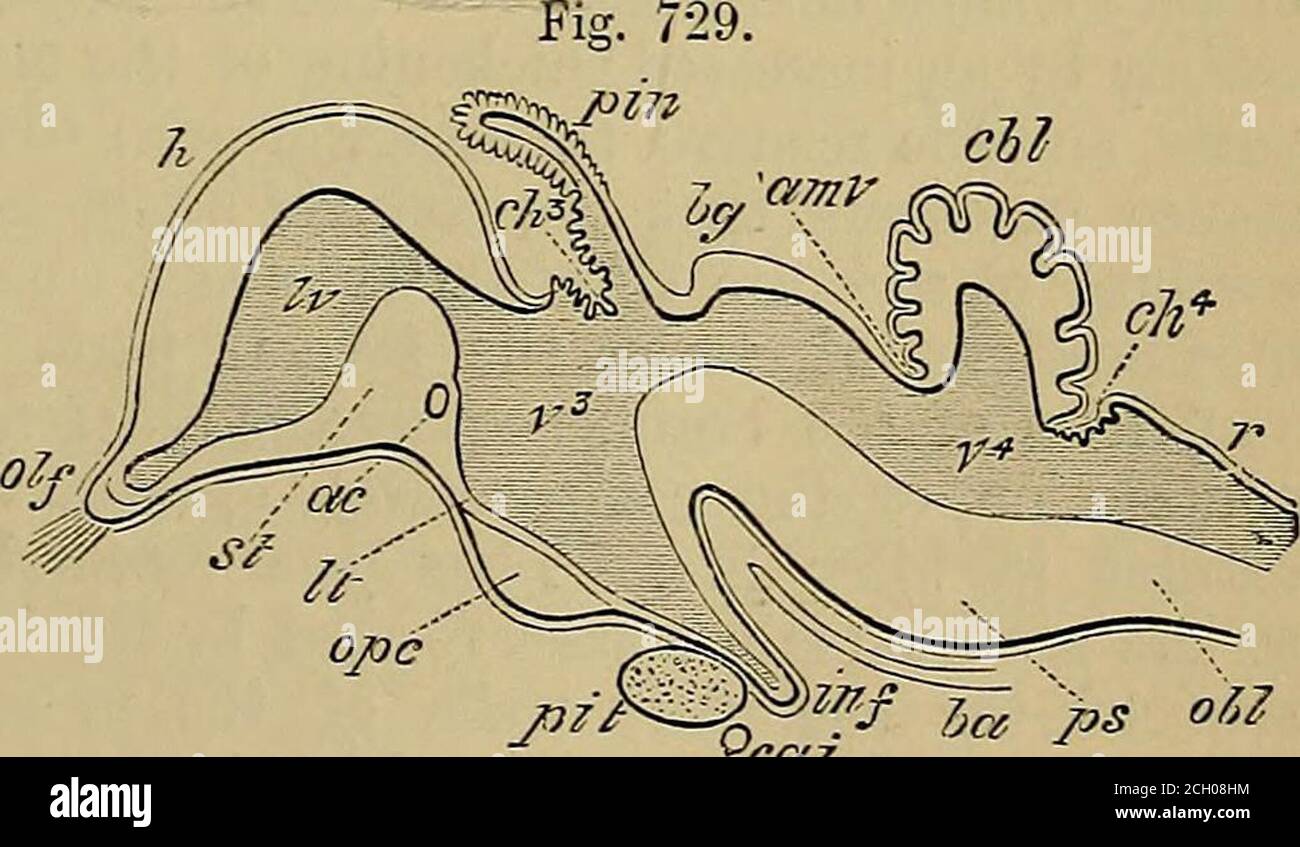

RM2ANFGX0–Quain der Elemente der Anatomie. ring Abb. 729.-op ein Bild. 729. Längsschnitt durch das Gehirn OFA KÜKEN VON ZEHN DATS. (Nach Mihalkovics.) h, zerebralen Hemisphäre; olf, oKactory lobe und Nerv; St, Corpus striatum; iv, lateralventricle; ac, anterior com-missure; Er, der Lamina terminalis; ope, Optic commissure; Grube, der Hypophyse; inf inf Undi-bulum; Cai, interne carotidartery; v^, dritten Ventrikel; ch?, Choroid plexus dritter Ventrikel; Pin, zirbeldrüse; Ijg, Korpora bigemina; amv, anterior medullary Velum; unten - n - hich zwei letzte Referenzen sind das Aquädukt von Sylvius und crur

RM2CH08HM–. Quains Elemente der Anatomie . Enient zu bringen Feige. 729. – UMRISS EINES LÄNGSSCHNITTS DURCH DAS GEHIRN OFA-KÜKEN VON ZEHN DATS. (Nach Mihalkovics.) h, zerebrale Hemisphäre ; Olf, olfaktorische Lappen und Nerven ; st,corpus striatum ; IV, lateralventricle; ac, anterior com-misure; Es, lamina terminalis;op, optic commissure ; Piit,pituitäre Drüse ; inf, infundi-bulum ; cai, interne cardartery ; ?••*, dritte Oticle ; Plexus ; Plexus ; Plexus ; Plexus hg, corpora bigemina ; amt anterior medullarj velum ;unter welchen zwei letzte Referenzen das Aquädukt von Sylvius und sind

RM2AWFNN9–Menschliche Anatomie, einschließlich Struktur und Entwicklung und praktische Überlegungen d in einem sagittalen mesialen Abschnitt (Abb. 910) wird jede dieser Teilungen als mit einem Teil des Systems der Kommunikation von Räumen verwandt angesehen, die als die dritten Ventrikel des Lateralands, der Aquädukt von Sylvius und der vierte Ventrikel die oben genannten Gehirnhemisphären ausdehnen. Durch den Hirnstamm und unter dem Kleinhirn bis zum zentralen Kanal des Rückenmarks. Da die lateralen Ventrikel zwei innumerieren, ist die Theirstellung im Zusammenhang mit den Gehirnhemisphären, in denen sie liegen, lateral zum m

RM2CDFE0C–. Elemente der physiologischen Psychologie; eine Abhandlung über die Aktivitäten und die Natur des Geistes, aus der physischen und experimentellen Gesichtspunkten. ide,die corpora quadrigemina. Die Kavität des Neuralrohres bleibt hier klein und bildet das Aquädukt, das den Viertmit dem dritten Ventrikel verbindet. Im Zwischenhirn dehnt sich das Aquädukt in den dritten Ventrikel aus; und hier wird wieder die dorsale Wand des Tubus zu einer breiten, dünnen Membran, die in den Ventrikel gefaltet und Blutgefäße mit sich trägt. Während die zerebralen Hemisphären ihr enormes Wachstum durchlaufen, dehnt sich die Kavität mit ihnen aus, andrema